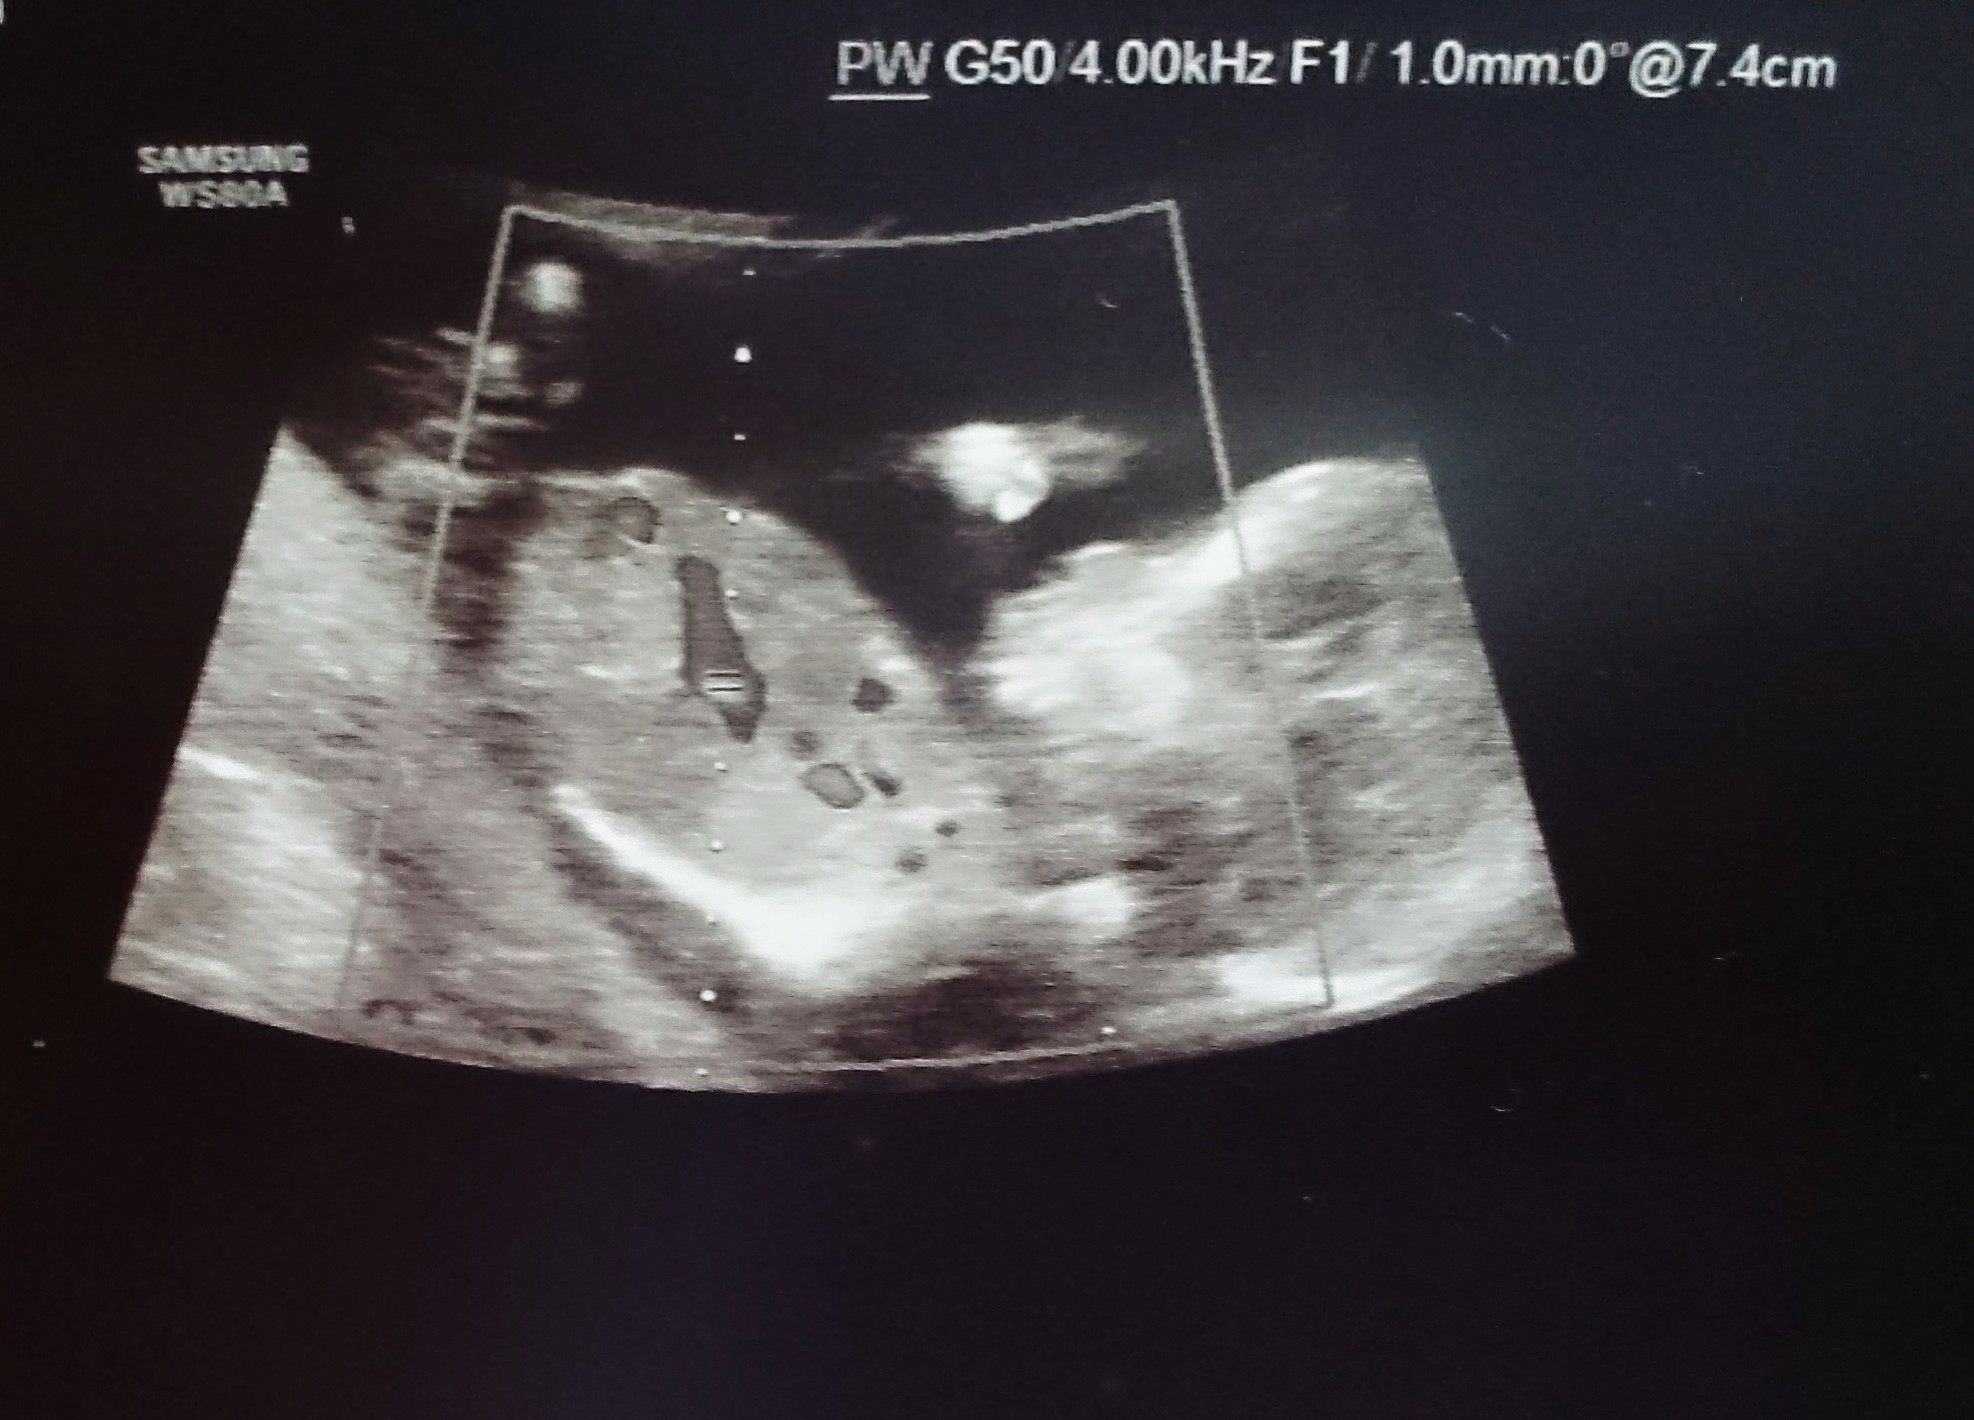

Witam w 19 tygodniu ciąży dowiedziałam się ze będę miała dziewczynkę w 20 tyg okazało się jednak , że to chłopak. Sama już nie wiem bo na jednym usg widać na pewno dziewuche a na drugim chłopca. Może to pempowina ?? Może ktoś mi pomoże rozwiązać ta zagadkę

Załączniki

• 4A8F5FF1-76CA-4DE0-AC12-5EDF08E820F2.jpg

4A8F5FF1-76CA-4DE0-AC12-5EDF08E820F2.jpg

596,4 KB · Wyświetleń: 23 774